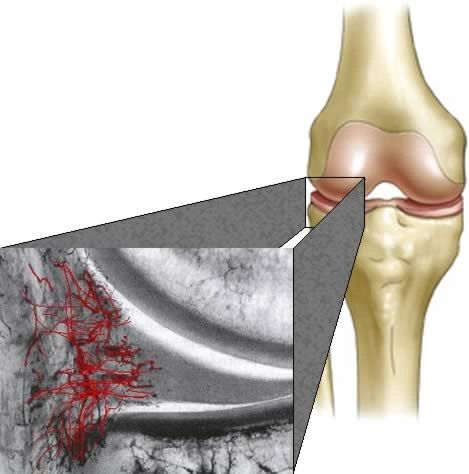

- Meniscus Surgery

- Meniscus Surgery 2